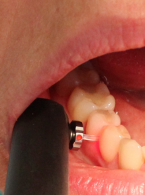

Podczas leczenia endodontycznego zęba 37 (dolny lewy drugi ząb trzonowy żuchwy) u 48-letniego mężczyzny pacjent zasygnalizował ból. Doszło do tego w trakcie wypełniania kanału korzeniowego pastą jodoformową. Ból obejmował lewą stronę twarzy, promieniował do pozostałych zębów lewej strony żuchwy i do okolicy lewego kąta ust. Na zdjęciu zębowym wykonanym bezpośrednio po pojawieniu się bólu zdiagnozowano zacienienie rzutujące się w przebiegu kanału żuchwy. Jakie powinno być postępowanie po przepchnięciu materiału do kanału żuchwy i jak można uniknąć takiego powikłania?